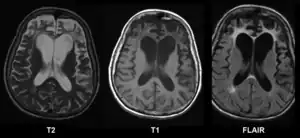

| Brain MRI of a female of 65 years with frontotemporal dementia. Cortical and white matter atrophy of the frontal lobes is clear in all images. | |